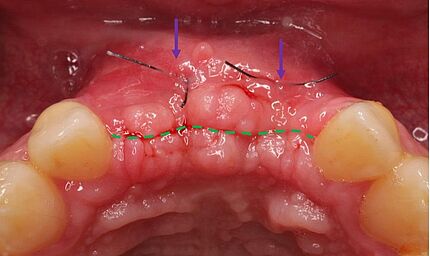

In den letzten Jahren ist eine Zunahme des Interesses an Knochenaugmentationen mit nicht erhaltungs- würdigen Zähnen erkennbar. Das Verwerfen von extrahierten Zähnen ist zurzeit noch tägliche Routine in Zahnarztpraxen und Kliniken. Dieser Fallbericht illustriert die Situation eines 62-jährigen Patienten, bei dem nach Entfernung der Oberkieferfrontzähne der Alveolarfortsatz einen komplexen knöchernen Defekt aufwies. Die Schaltlücke wurde zweizeitig rekonstruiert. Hierbei wurde der knöcherne Defekt mittels der Tooth Shell Technique nach Korsch unter Verwendung von autologem Dentin rekonstruiert und mit zwei Implantaten sowie Implantatkronen prothetisch versorgt. Abschließend erfolgte eine Transplantation von freier keratini-sierter Schleimhaut zur Rekonstruktion des Vestibulums und zur Stabilisierung der periimplantären Mukosa.